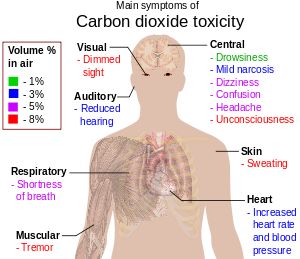

Hypercapnea – is also known as hypercarbia. It is a condition related to high carbon dioxide levels in the body. Carbon-dioxide can get built up in the blood if the body doesn’t successfully get rid of it within time. Conditions that either increase the levels of carbon-dioxide in the body or prevent the waste carbon-dioxide from getting to the lungs and discarded are usually the main causes of hypercapnea. Illnesses related to lung, brain, muscles and nerves are usually the most common causes. Hypercapnia is different to hypoxemia as hypercapnia is the condition with high carbon-dioxide levels in blood whereas hypoxemia is low oxygen levels in blood.